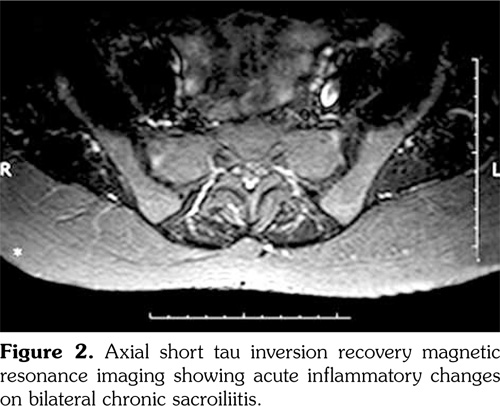

Schirmer’s test (right 3 mm, left 5 mm) and tear break-up time values (right 5 seconds, left 6 seconds) were consistent with dry eye. Lumbosacral spine X-ray showed grade III sacroiliitis on the right side and grade II sacroiliitis on the left side (Figure 1). Sacroiliac magnetic resonance imaging revealed acute inflammatory changes and bilateral sacroiliitis with moderate chronic features (Figure 2).